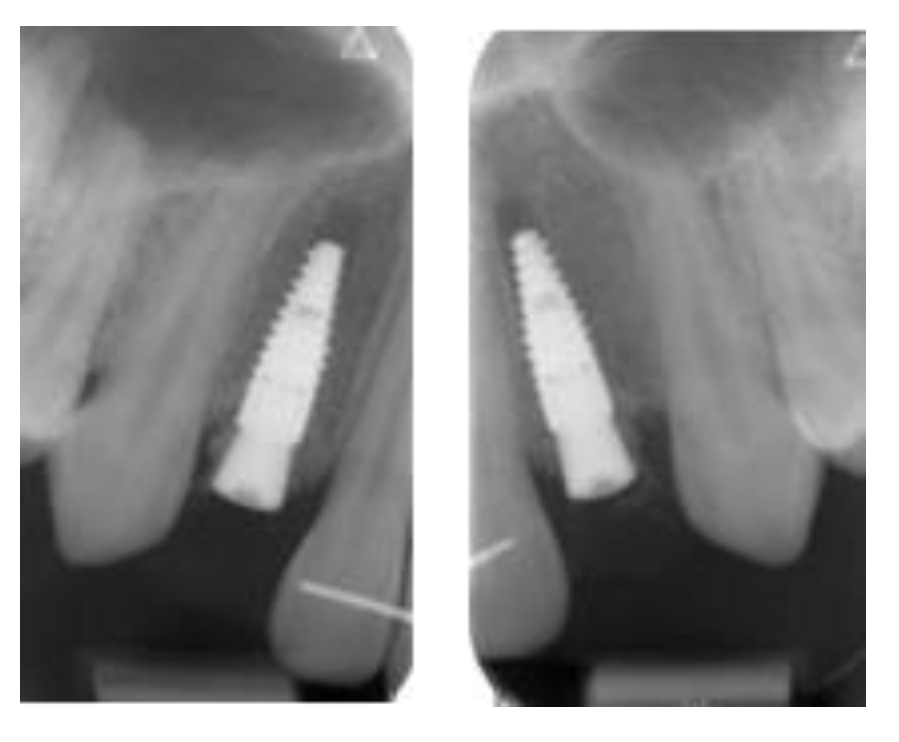

3.2. Marginal Bone Level Outcomes

| Mesial Marginal Bone Level (2D) [mm] after Immediate Placement | ||||||||

|---|---|---|---|---|---|---|---|---|

| Patient | 1 | 2 | 3 | 4 | 5 | Median | IQR | |

| Implant position | 45 | 35 | 45 | 45 | 13 | 23 | NA | NA |

| Post-OP mesial | 1.8 | 0.0 | 0.1 | 3.0 | 0.4 | 0.4 | 0.4 | 0.18–1.45 |

| 1 year mesial | 0.6 | 0.0 | 0.1 | 1.5 | 0.1 | 0.1 | 0.1 | 0.1–0.48 |

| Post-OP distal | 1.2 | 0.0 | 0.1 | 3.0 | 0.4 | 0.4 | 0.4 | 0.18–1.0 |

| 1 year distal | 0.6 | 0.0 | 0.1 | 1.5 | 0.2 | 0.0 | 0.2 | 0.03–0.5 |

| Marginal Bone Level (2D) [mm] after Delayed Placement | ||||||||

| Implant position | 35 | 45 | 35 | 35 | 35 | 45 | NA | NA |

| Post-OP mesial | 2.0 | 1.0 | 0.2 | 0.6 | 0.2 | 0.2 | 0.4 | 0.2–0.9 |

| 1 year mesial | 1.6 | 0.5 | 0.0 | 0.3 | 0.1 | 0.1 | 0.3 | 0.1–0.45 |

| Post-OP distal | 0.0 | 0.5 | 0.0 | 0.6 | 0.1 | 0.1 | 0.1 | 0.03–0.4 |

| 1 year distal | 0.0 | 0.2 | 0.0 | 0.3 | 0.1 | 0.1 | 0.1 | 0.03–0.18 |